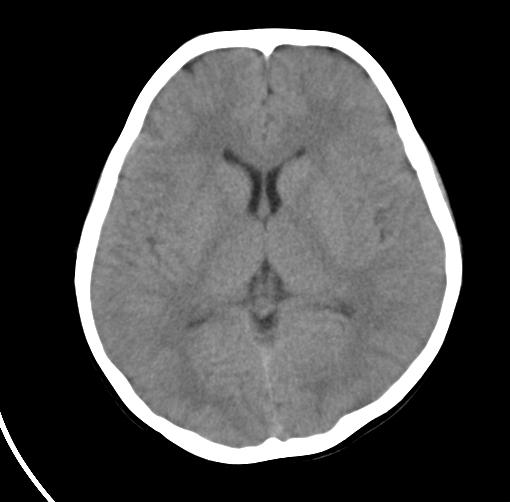

以下是引用sunjh2266在2007-7-31 23:35:00的发言:[br]脉络膜裂,是胚胎发育过程中脉络襞突入侧脑室下角构成脉络丛时形成,位于丘脑下部与海马之间,走行与海马平行。脉络裂内侧通于环池,外侧为侧脑室下角,前面是海马钩及杏仁体,后部与海马沟交通。脉络裂内有参与组成侧脑室脉络丛的脉络膜前动脉及脉络膜后外动脉及其分支走行。[br] mri轴位像,在大脑脚的前外侧多能显示脉络裂的前部,呈左右走行的含脑脊液间隙,前后内外分别与杏仁体、海马、海马钩及侧脑室下角相邻(图1);冠状位像,在扫及脑干的多个层面上,脉络裂均可被清晰显示,因而是显示脉络裂的最佳扫描方式。偏前的部分层面还可见到呈切迹状的海马沟走行于海马旁回内上方;矢状位像,海马旁回上方可见一分叉状裂隙,类似一斜卧的“入”字,接近水平走行的一撇为脉络裂,而由后上向前下走行的一捺为从扣带沟延续而来的海马沟。[br] [br]